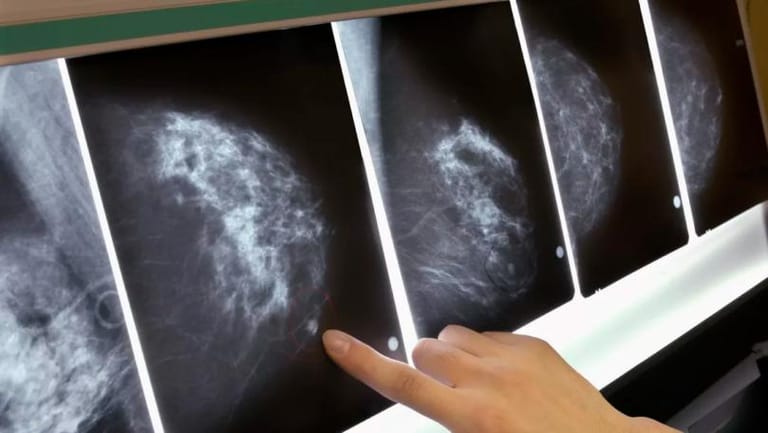

An artificially intelligent Google system could be better at spotting breast cancer than expert radiologists, a new study suggests.

The research saw the computer, which was created by Google’s AI experts, compared with medical professionals as they both screened mammograms.

It found that the AI was largely as good as the humans at spotting incidences of breast cancer - and that it was much better at avoiding false positives.

The team, which included researchers at Imperial College London and the NHS, trained the system to identify breast cancers on tens of thousands of mammograms. They then compared the system’s performance with the actual results from a set of 25,856 mammograms in the UK and 3,097 from the US

The study showed the AI system could identify cancers with a similar degree of accuracy to expert radiologists, while reducing the number of false positive results by 5.7 per cent in the US-based group and by 1.2 per cent in the British-based group.

It also cut the number of false negatives, where tests are wrongly classified as normal, by 9.4 per cent in the US group, and by 2.7 per cent in the British group.

In a separate test, the group pitted the AI system against six radiologists and found it outperformed them at accurately detecting breast cancers.